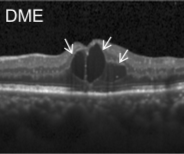

Eye diseases or ocular dysfunctions are fairly frequent in the general population, particularly among the elderly. The most significant anomalies in the eyes are choroidal neovascularization (CNV), diabetic macular edema (DME), and drusen accumulation in the macular region. In the recent decade, optical coherence tomography (OCT) has become one of the most rapidly evolving medical imaging technologies which can capture blood flow, polarization state, structural data, elastic properties, and molecular content, among other things, in biological tissues [1]. Optical diffraction and absorbance of biological tissues can be accurately measured with OCT and thus some diagnostic measures benefit from it.

Figure 1: Representative Optical Coherence Tomography (OCT) Images (a) CNV (b) DME (c) DRUSEN (d) NORMAL

Optical coherence tomography (OCT) images were selected from retrospective cohorts of adult patients from different hospitals around the world. OCT Images are labeled as (disease)-(randomized patient ID)-(image number by this patient) [11] and Fig 1 shows some examples of OCT images. Image properties are presented in Table II and the distribution of image quantity is presented in Table III. Custom image generators resize images to 224x224x3 and normalize them